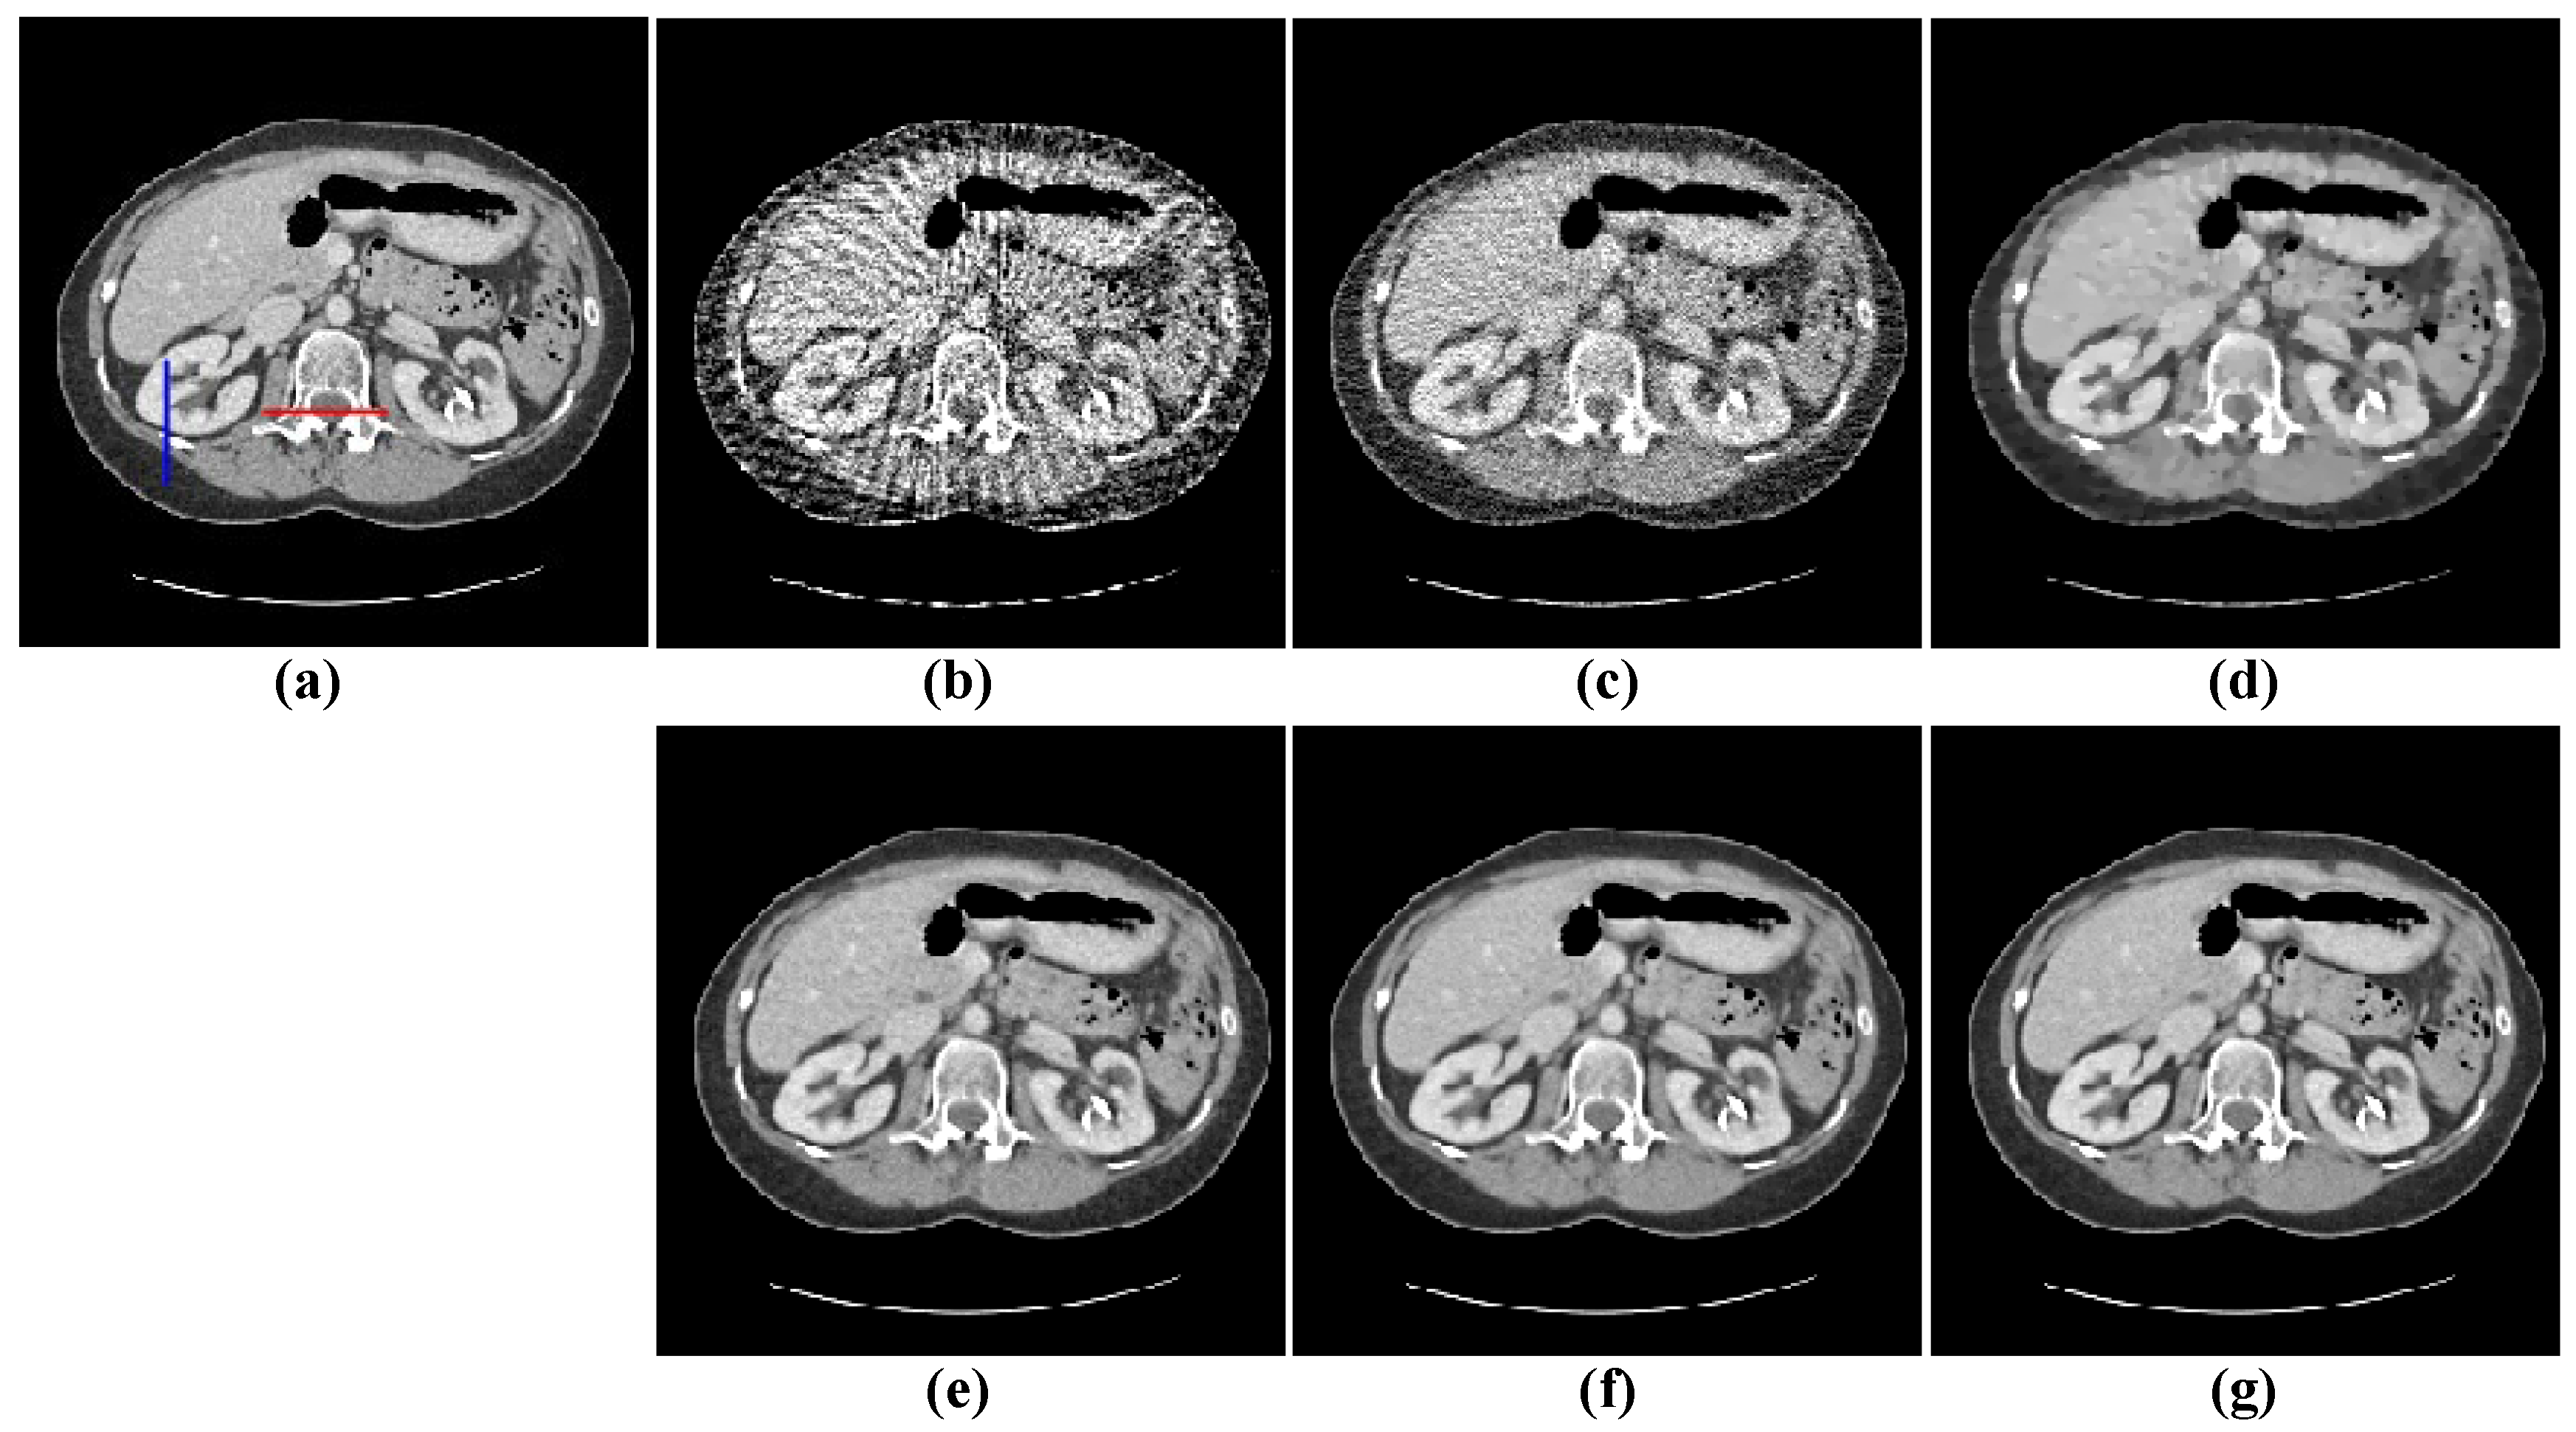

Figure 12. 80-views reconstruction results of abdomen image: (a) ground truth, (b) FBP, (c) OS-SART, (d) TV, (e) PICCS, (f) TVPI-G, and (g) NPICCS. The display window is [−150 250] HU.

The second image reconstruction experiment is conducted on an abdomen image with more image details to show the feasibility of our algorithm for SVCT reconstruction, as shown in Figure 9. We extracted 80, 64, and 48 views from a full scan and set the parameters as follows: a = 0.5, γ1 = 0.1, and γ2 = 0.06. The reconstructed results using different algorithms are shown in Figure 10, Figure 11 and Figure 12. As can be seen from the figures, our algorithm performs better than other algorithms in preserving small structures and reducing noise. Specifically, FBP reconstruction results contain severe artifacts as displayed in Figure 10b, Figure 11b and Figure 12b. OS-SART reconstruction results also have obvious noise as displayed in Figure 10c, Figure 11c and Figure 12c. TV has a better performance than FBP and OS-SART, but the result has blocky artifacts, as displayed in Figure 10d, Figure 11d and Figure 12d. The PICCS and TVPI-G algorithms have an improvement in image quality, but fine image structures are losing detail and some edge information is blurring, as displayed in Figure 10e,f, Figure 11e,f and Figure 12e,f. As can be observed from Figure 10g, Figure 11g and Figure 12g, the proposed algorithm performs better not only in preserving edge and image details, but also in reducing noise.

Subsequently, we select two ROIs, marked by a red box as shown in Figure 10a and Figure 11a, and zoom in on them to show the results. The enlarged ROIs are shown in Figure 13. It could be observed that our algorithm can reconstruct some of the important tissues shown by the arrows, which are blurred or difficult to see in other ROIs. To show the accuracy of the different methods for local reconstruction of CT images, we plot the 1D line intensity distribution in CT images reconstructed from 80 projections in two regions (shown as blue and red lines in Figure 12a); the curves are as shown in Figure 14. Visually, it can be seen that the line intensity distribution of the image reconstructed by the proposed method is the closest to the original CT image in these two regions. In comparison, the proposed reconstruction algorithm in this paper is more accurate. At the same time, the red enlarged part of the figure indicates the edge area, from which it can be seen that the proposed algorithm has better performance in edge protection.